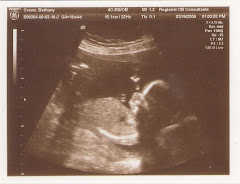

This is Baby Crews looking at the camera.